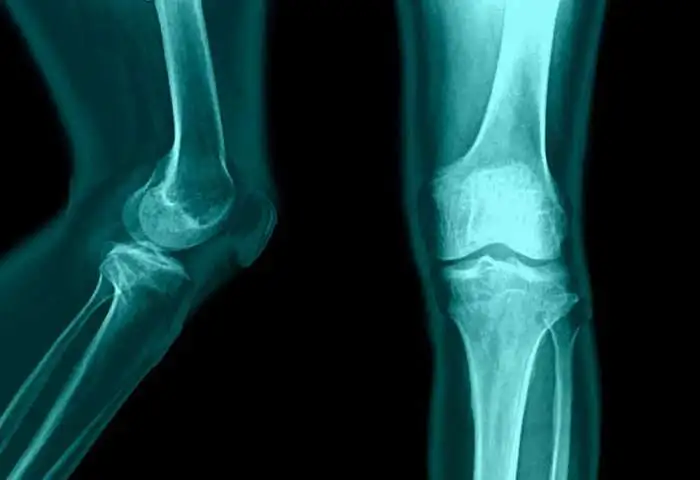

Дыдыкина И.С. "Портрет пациента с мышечно-скелетной болью в ревматологии"

В сегодняшней лекции врач ревматолог Дыдыкина Ирина Степановна, к.м.н., ведущий научный сотрудник

ФГБНУ НИИР им. В.А.Насоновой, расскажет об основных портретах пациентов с титульными ревматическими заболеваниями, которые чаще всего встречаются в клинической практике врача ревматолога и терапевта.